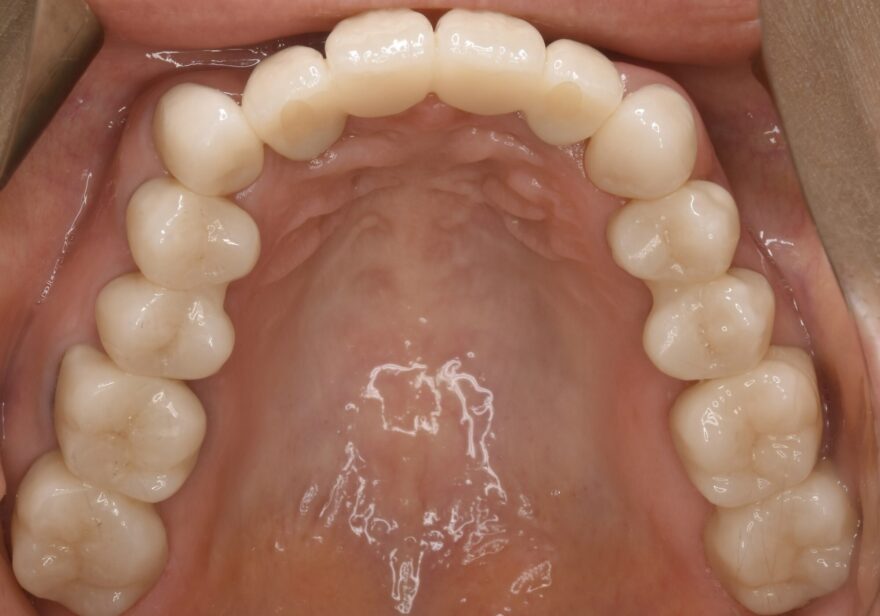

治療後の口腔内写真

白く輝く美しい歯が入りました。

長期にわたる理想的な噛み合わせが付与されました。

裏から見ても上の前歯のインプラントブリッジは自然な仕上がりです。